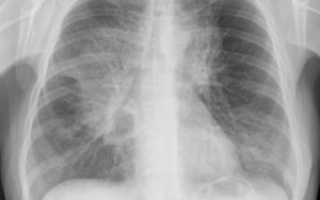

Рентген легких позволяет получить черно-белое изображение органов грудной клетки, с помощью которого специалист имеет возможность увидеть патологические изменения и подобрать подходящее лечение.

Признаков, по которым можно диагностировать патологию, много, но выделяют три самых главных – просветление легочного поля или отдельной части, затемнение легочного поля или части и изменение корневого и легочного рисунка.

Затемненные участки легочной ткани на снимках вызваны уплотнением мягких тканей, что приводит к снижению или полному отсутствию воздушности.

Очаги уплотнения сильнее поглощают рентгеновские лучи, за счет чего на фоне светлых легочных полей появляются тени, или, говоря языком рентгенологов, участки затемнения.

Такие изменения на рентгеновских снимках характерны для многих заболеваний бронхолегочной системы, при этом от величины поражения зависит форма и объемы затемнения. Тень по всему объему легкого чаще всего сопровождает ателектаз легкого и закупорку главного бронха.

Острое воспаление легких всегда сопровождается инфильтрацией мягких тканей. В зоне воспаления происходит заполнение альвеол экссудатом, в связи с чем снижается воздушность легких, а патологически измененные участки интенсивнее поглощают рентгеновские лучи.

Рентгеновское исследование является основным способом диагностики пневмоний, так как оно позволяет выявить степень распространения воспалительного процесса, интенсивность изменений в корнях легких, плевре и диафрагме.

На рентгене видно тень и просветление, так как снимок является негативом пленки. Тень указывает на уплотненные области легких, а белые пятна указывают на скопление воздуха или жидкости. Для получения полной картины процедуру проводят в двух или трех проекциях (прямая, косая, боковая). Туберкулез на рентгене лёгких хорошо виден на самой ранней стадии.